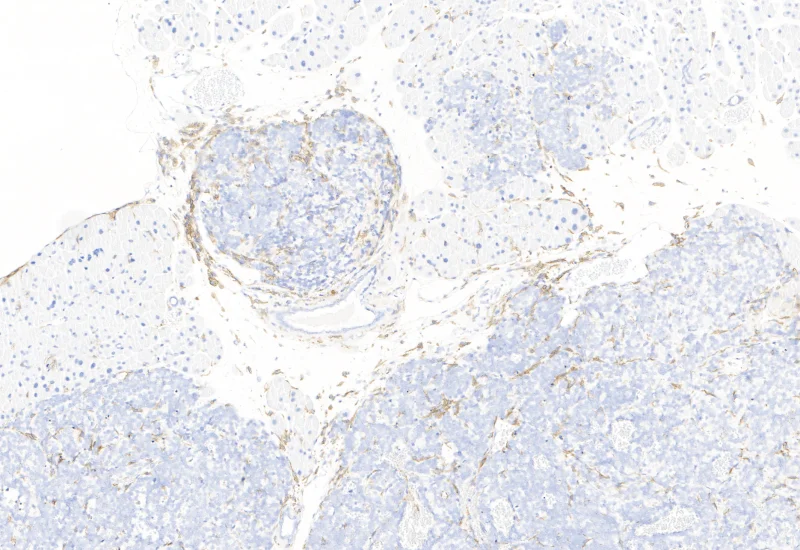

IHC Tumor Macrophages

Segment tissue into tumor and healthy areas, detect CD68+ macrophages, and quantify macrophage area within each tissue compartment.

The IHC Tumor-Macrophages APP provides tissue detection including separation into tumor tissue and healthy tissue. It detects macrophages based on a specific staining (e.g. CD68). The APP outputs the area of macrophages within tumor tissue and healthy tissue.

Image courtesy of Dr. Patrick Michl, Dr. Maren Egidi and Dr. Heidi Griesmann, Universitätsklinikum Halle (Saale)

Original Image